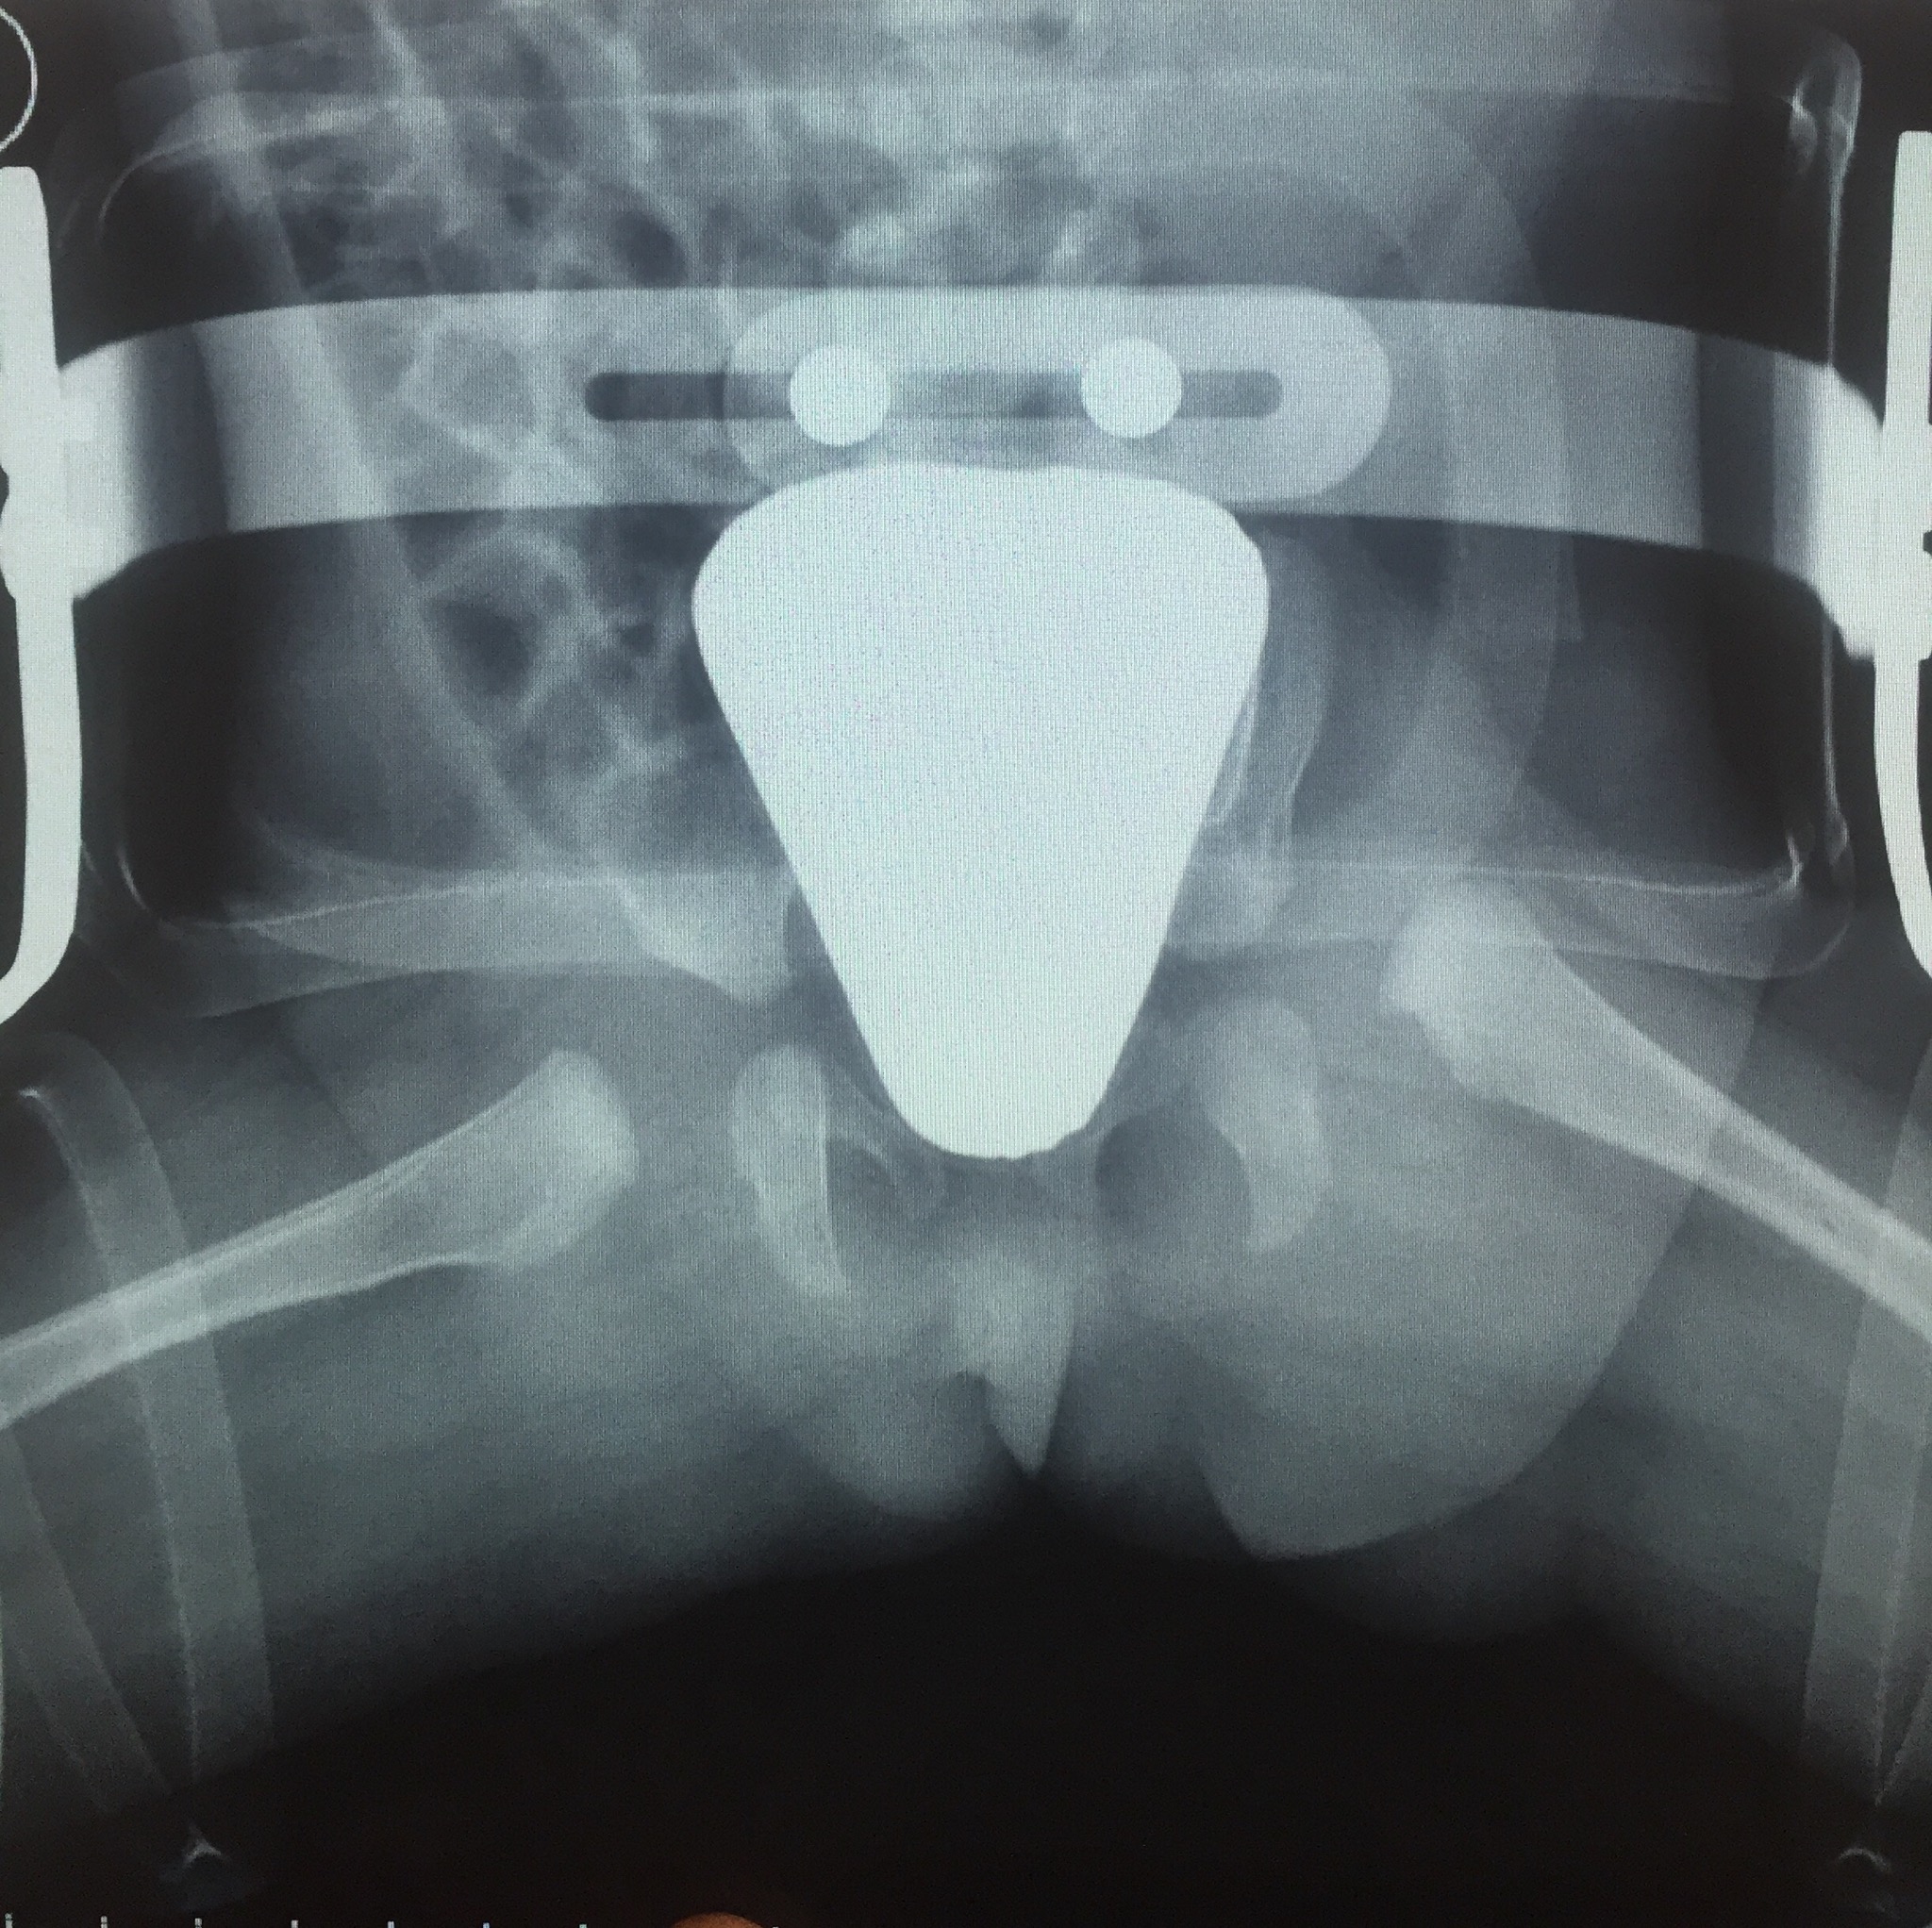

A mia figlia che ora ha 3 mesi è stata diagnosticata displasia anca sinistra . La diagnosi risale alla eco fatta a 1 mese e mezzo dopo ortolani positiva. La eco refertava anca tipo 2D cn grado alfa 43 e beta >77 Questa la prima radiografia dopo 1 mese e dieci giorni di divaricatore milgram. Sarei grato se qualcuno potesse dirmi che evoluzione c’è ad oggi e le condizioni . Non riesco a capire se sino gravi o no. Purtroppo vedrò L ortopedico solo fra una settimana ...